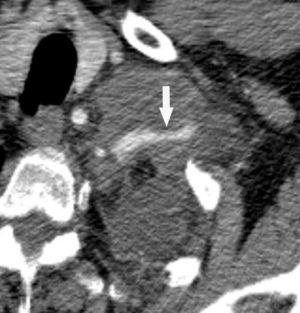

La precisión de la TC para predecir la afectación ganglionar mediastínica, pese a la ayuda que suponen las reconstrucciones MPR y 3D en la valoración de determinados territorios ganglionares (espacio subcarinal, hilio o ventana aortopulmonar) (fig. 11), sigue teniendo muchas limitaciones. El único criterio que se emplea para considerar que un ganglio es patológico es el tamaño (cuando el eje corto es mayor de 10 mm, salvo en el espacio subcarinal que se acepta hasta 12 mm). El empleo únicamente de criterios de tamaño hace que la TC sea una técnica poco precisa en la valoración de la afectación ganglionar. En un metaanálisis reciente13 la sensibilidad global de la TC para estadificar el mediastino fue de un 57%, con una especificidad del 82%, un valor predictivo positivo (VPP) del 56% y un valor predictivo negativo (VPN) del 83%. Lo que es innegable es la capacidad de la TC para mostrar un mapa de los ganglios tanto hiliares como mediastínicos (fig. 12), lo cual es de gran utilidad en la determinación del factor N. La valoración del territorio hiliar puede ser compleja por la agrupación de estructuras vasculares, por lo que además de la opacificación adecuada de éstas, es de utilidad la identificación de la pérdida del ángulo de la bifurcación (carina secundaria), ya que el eje corto significativo en este territorio es de 3 mm. Como ya hemos comentado, también es de gran ayuda en esta localización el empleo de reconstrucciones (fig. 11)5.

Fig. 11.--N2. (A) Corte axial de tomografía computarizada (TC) con contraste. Nódulo heterogéneo en el segmento 6 del lóbulo inferior derecho con infiltración de la vena pulmonar inferior (flecha). (B) En la reconstrucción de volumen se ponen de manifiesto la infiltración tumoral de la vena pulmonar (flecha negra), la adenopatía hiliar (asterisco) y una adenopatía calcificada lobar superior derecha (flecha blanca).